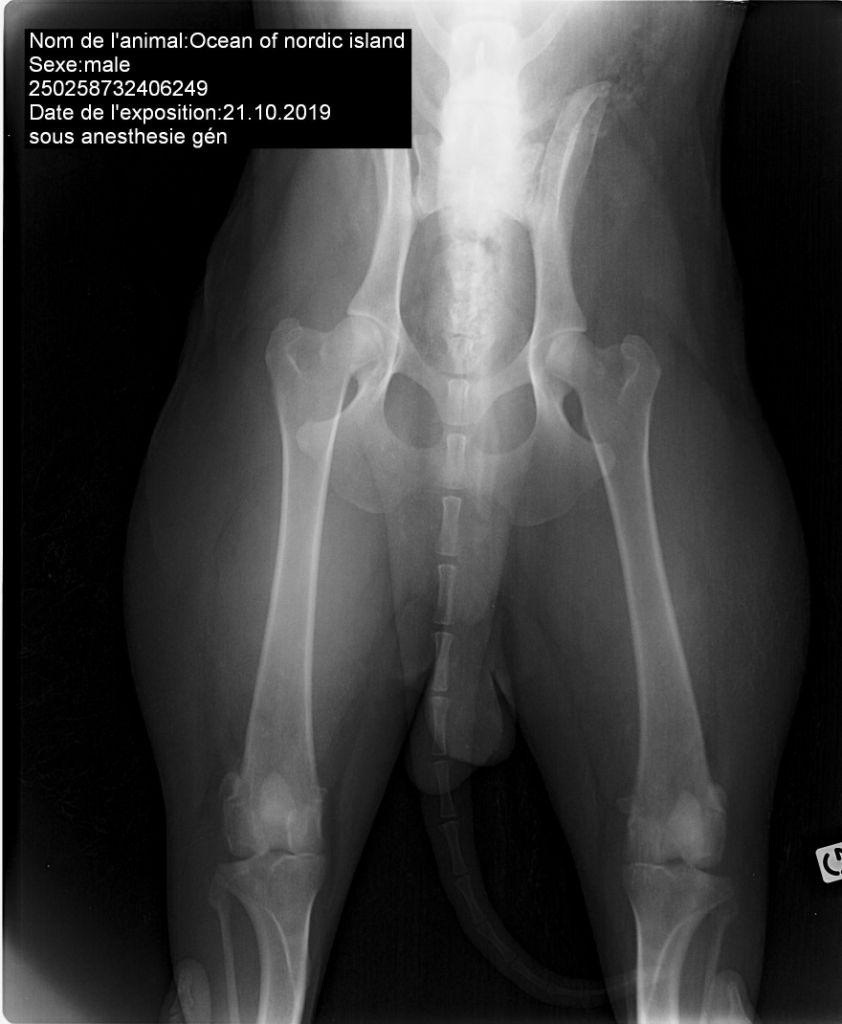

Identifié ADN - ouiluxation de rotule - indemneDandy walker - Exempt (par antagène)Dentition - DCCMyélopathie dénégérative - Exempt ( par antagène)dysplasie de la hanche - indemne, A